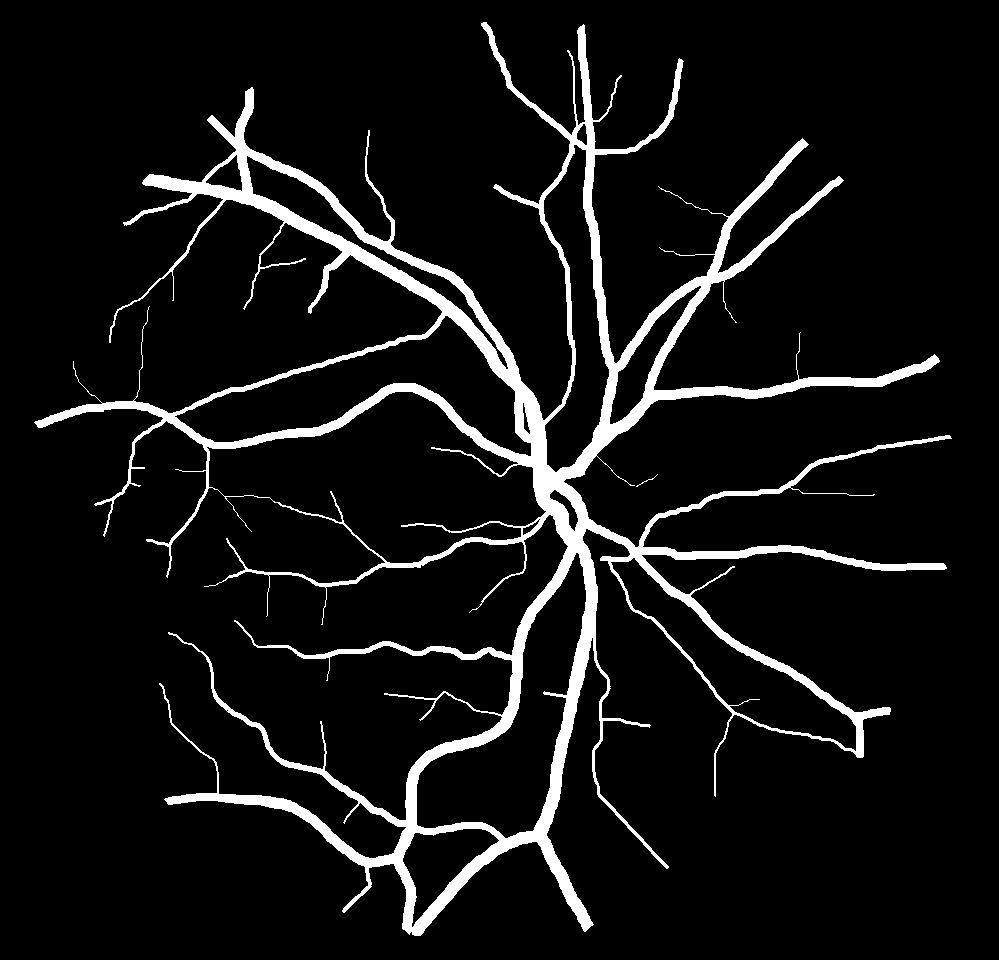

As reported in Table IV, we compared the SegRAVIR model against competing deep learning-based segmentation approaches on the RAVIR dataset. Evidently, SegRAVIR outperforms these methods as judged by all metrics for artery and vein classes with a healthy margin. In terms of Dice score, SegRAVIR outperforms CE-NET, IterNet and AG-Net by , and for artery segmentation and by , and for vein segmentation, respectively. Fig. 4 presents a qualitative comparison of the semantic segmentation outputs of SegRAVIR, CE-Net, and U-Net. Specifically, SegRAVIR yields more accurate vessel topology (i.e., thickness and orientation) segmentation with higher pixel-wise classification accuracy.

(a) (b) (c)